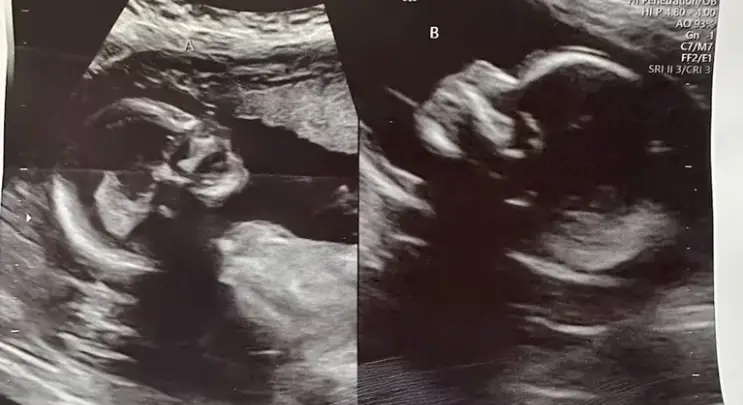

En un caso médico extraordinario, Kelsey Hatcher, una mujer estadounidense de 32 años, está embarazada de gemelas en úteros separados. Este hecho se registró en el Hospital de la Universidad de Alabama en Birmingham, Estados Unidos. Esto se debe a una condición llamada útero didelfo (uterus didelphys). La condición ocurre a 3 de cada 1.000 mujeres.

Hatcher está actualmente en la semana 34 de un embarazo que sus médicos han estado monitoreando meticulosamente desde su descubrimiento en mayo.

Sus médicos han enfrentado una situación sin precedentes, ya que cada útero podría contraerse en momentos distintos, lo que implicaría que las bebés nazcan con horas, días o incluso semanas de diferencia. Richard Davis, especialista en medicina materno-fetal que atiende a Hatcher, y la obstetra Shweta Patel, quien confirmó la presencia de un feto en cada útero, han adaptado el seguimiento del embarazo a la manera en que supervisarían uno de los gemelos, aunque reconocen la falta de guías clínicas debido a la singularidad del caso, según indicaron a The Washington Post.